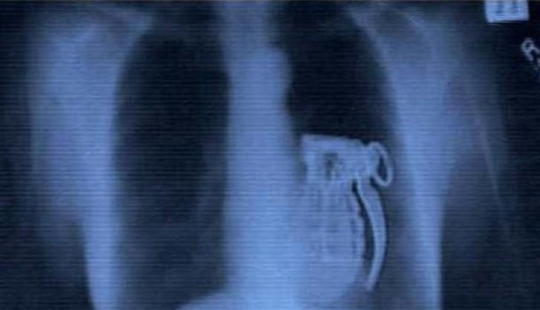

El pecho de silicona salvó la vida de su amante al detener ...

Resulta que los implantes mamarios de silicona pueden servir a su amante no solo como decoración, sino también como protección. ...